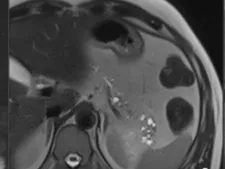

During this fellowship CT/MR technique as well as the different pathologies of the pancreas will be shown, in an interactive way, trying to illustrate the best technique according to the different clinical fields.

Most frequent as well as rare pancreatic pathologies will be shown. Diagnosis, differential diagnosis, staging and assessment of therapeutic response will be illustrated.

- Diagnostic approach to solid and cystic pancreatic tumours